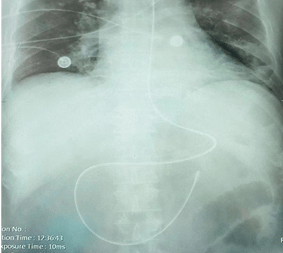

刚接班,就给一个胃排空差的患者盲法插了鼻肠管,腹部平片提示"c"形

鼻肠管腹部平片定位标准